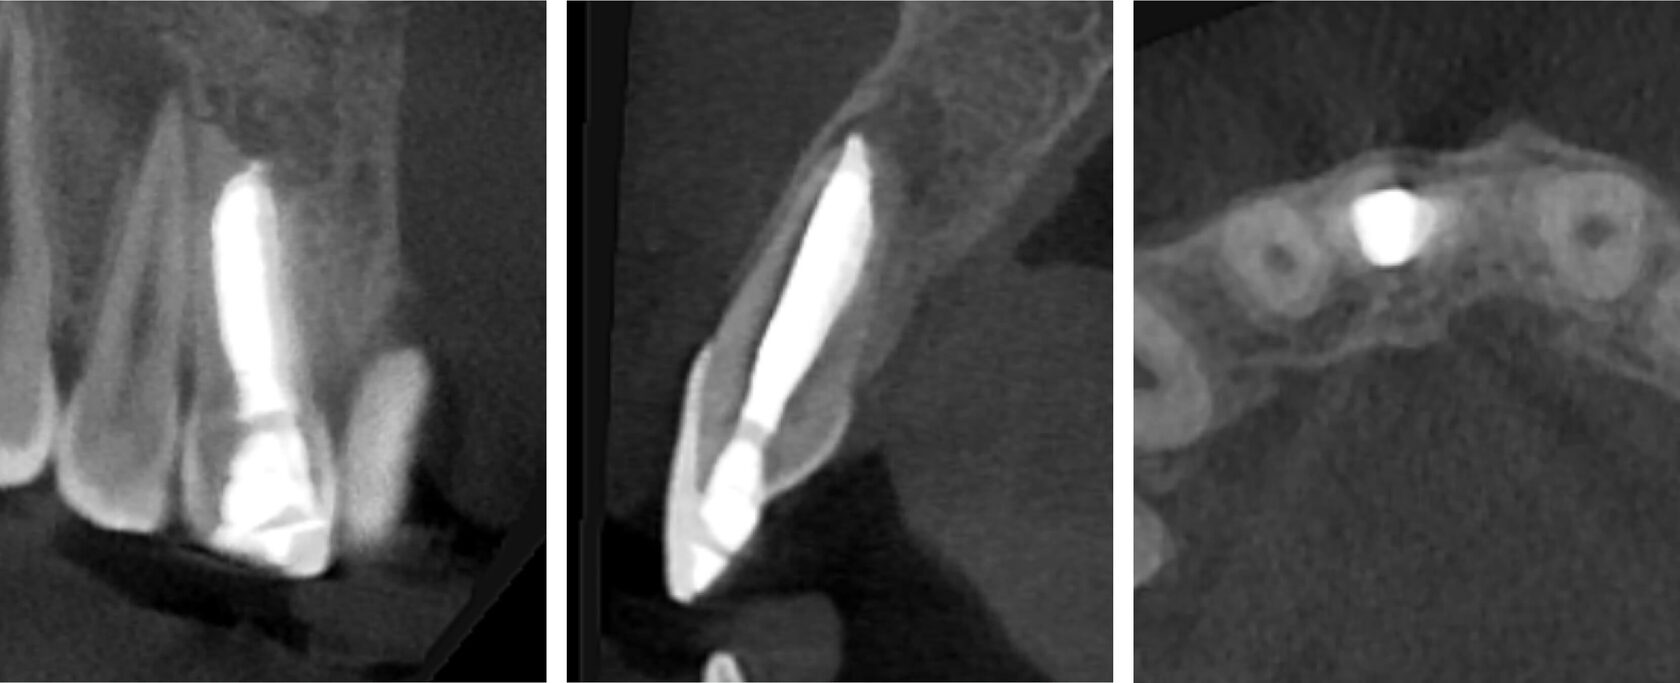

1. A pediatric patient presented with a history of dental trauma occurring approximately five years prior, for which no timely treatment had been provided. (Image 1)

2. Tooth #11 was diagnosed as non-vital with apical periodontitis, presenting extensive periapical bone destruction radiographically. In contrast, tooth #12 responded normally to vitality tests, confirming pulp vitality. (Image 2,3,4)